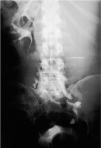

Fig. 1. Urografía intravenosa que muestra una duplicidad renoureteral bilateral, con hidronefrosis del sistema excretor superior izquierdo junto a un uréter inferior dilatado y tortuoso y un defecto de repleción vesical correspondiente a un ureterocele.